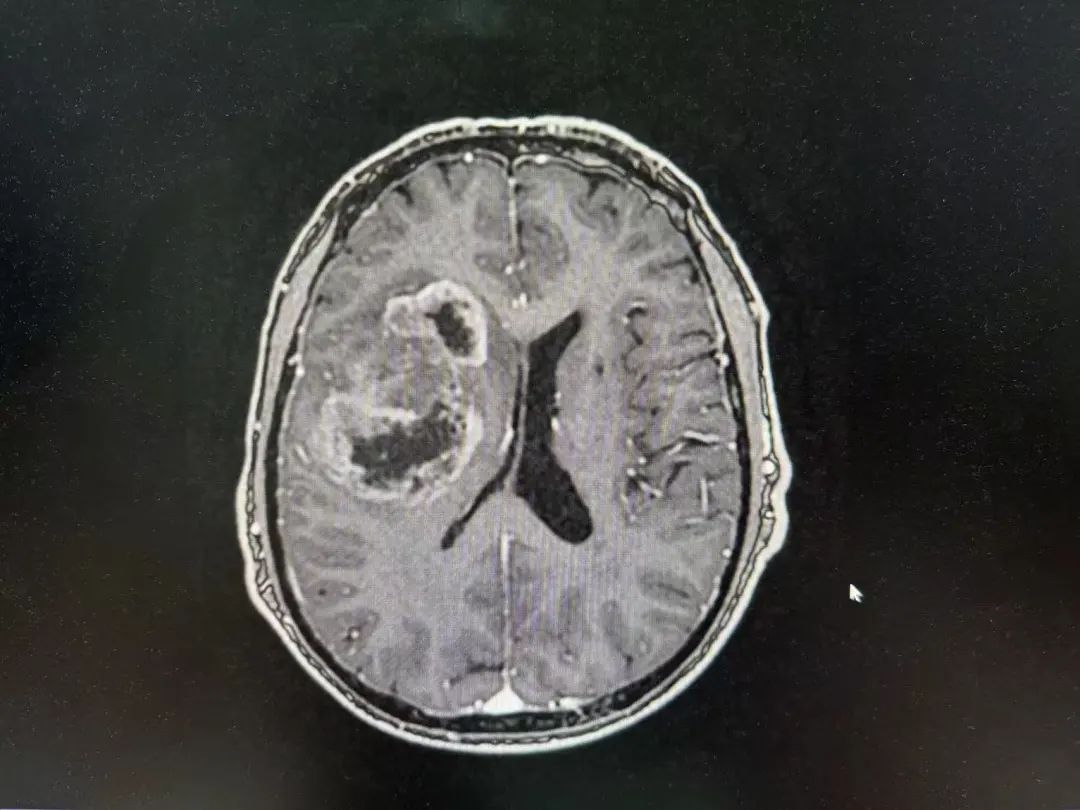

男性 | 67歲

主訴:左側(cè)口角流涎10天,左側(cè)肢體無(wú)力7天。

MR:右側(cè)大腦半球腫瘤性病變,考慮高級(jí)別膠質(zhì)瘤(大者大小約3.8cmx4.6cmx3.4cm)。